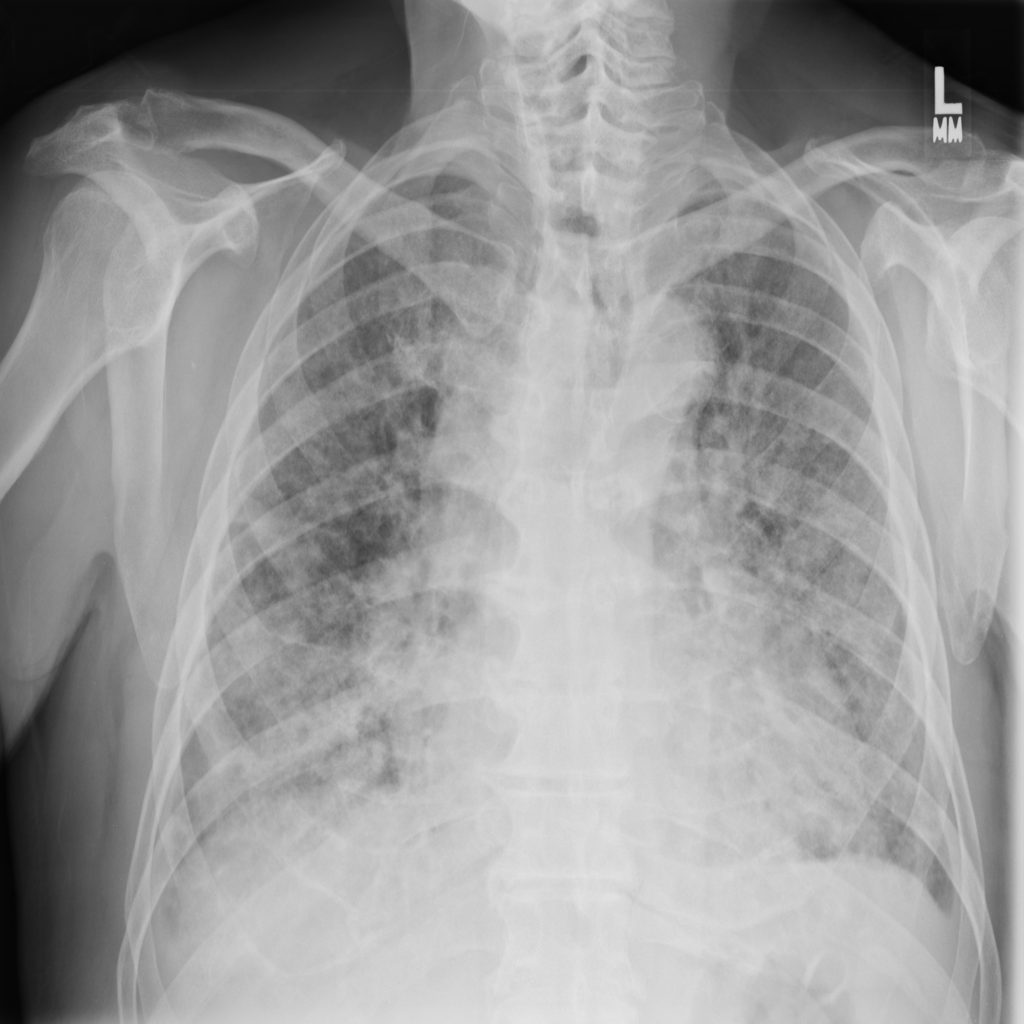

PAT-E828 · IMG-004Edema

PAT-E828 · IMG-004

AP